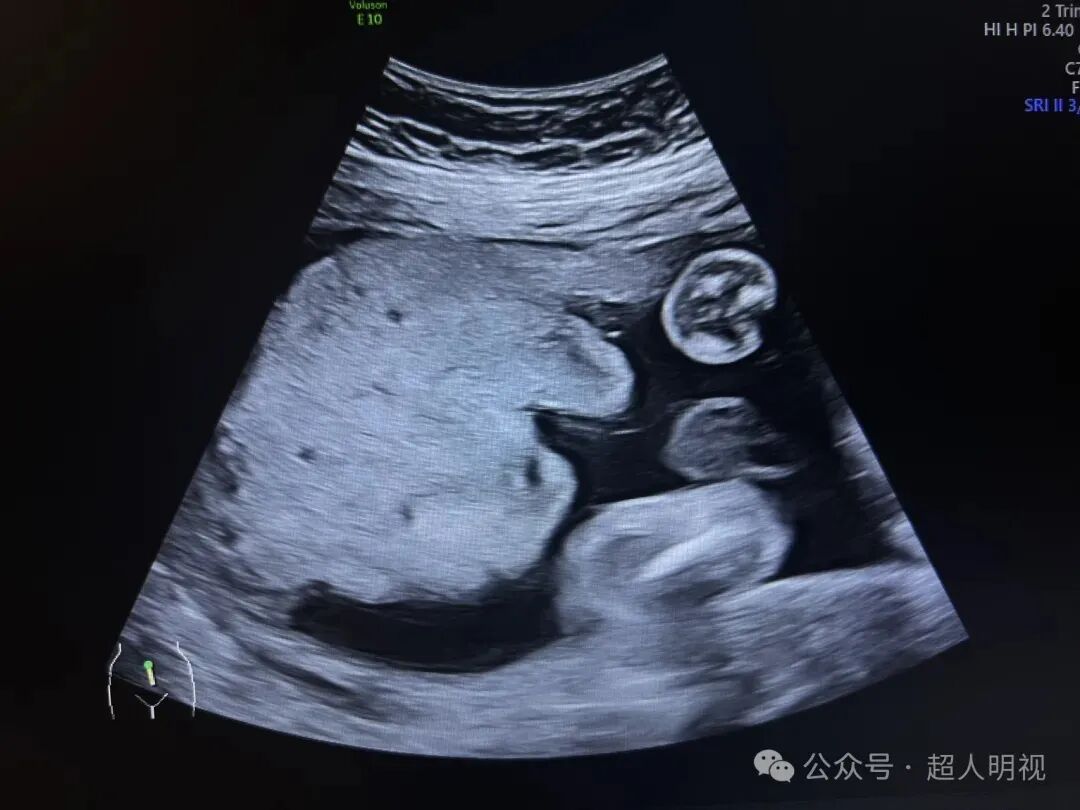

胎盘小而厚说明了啥?